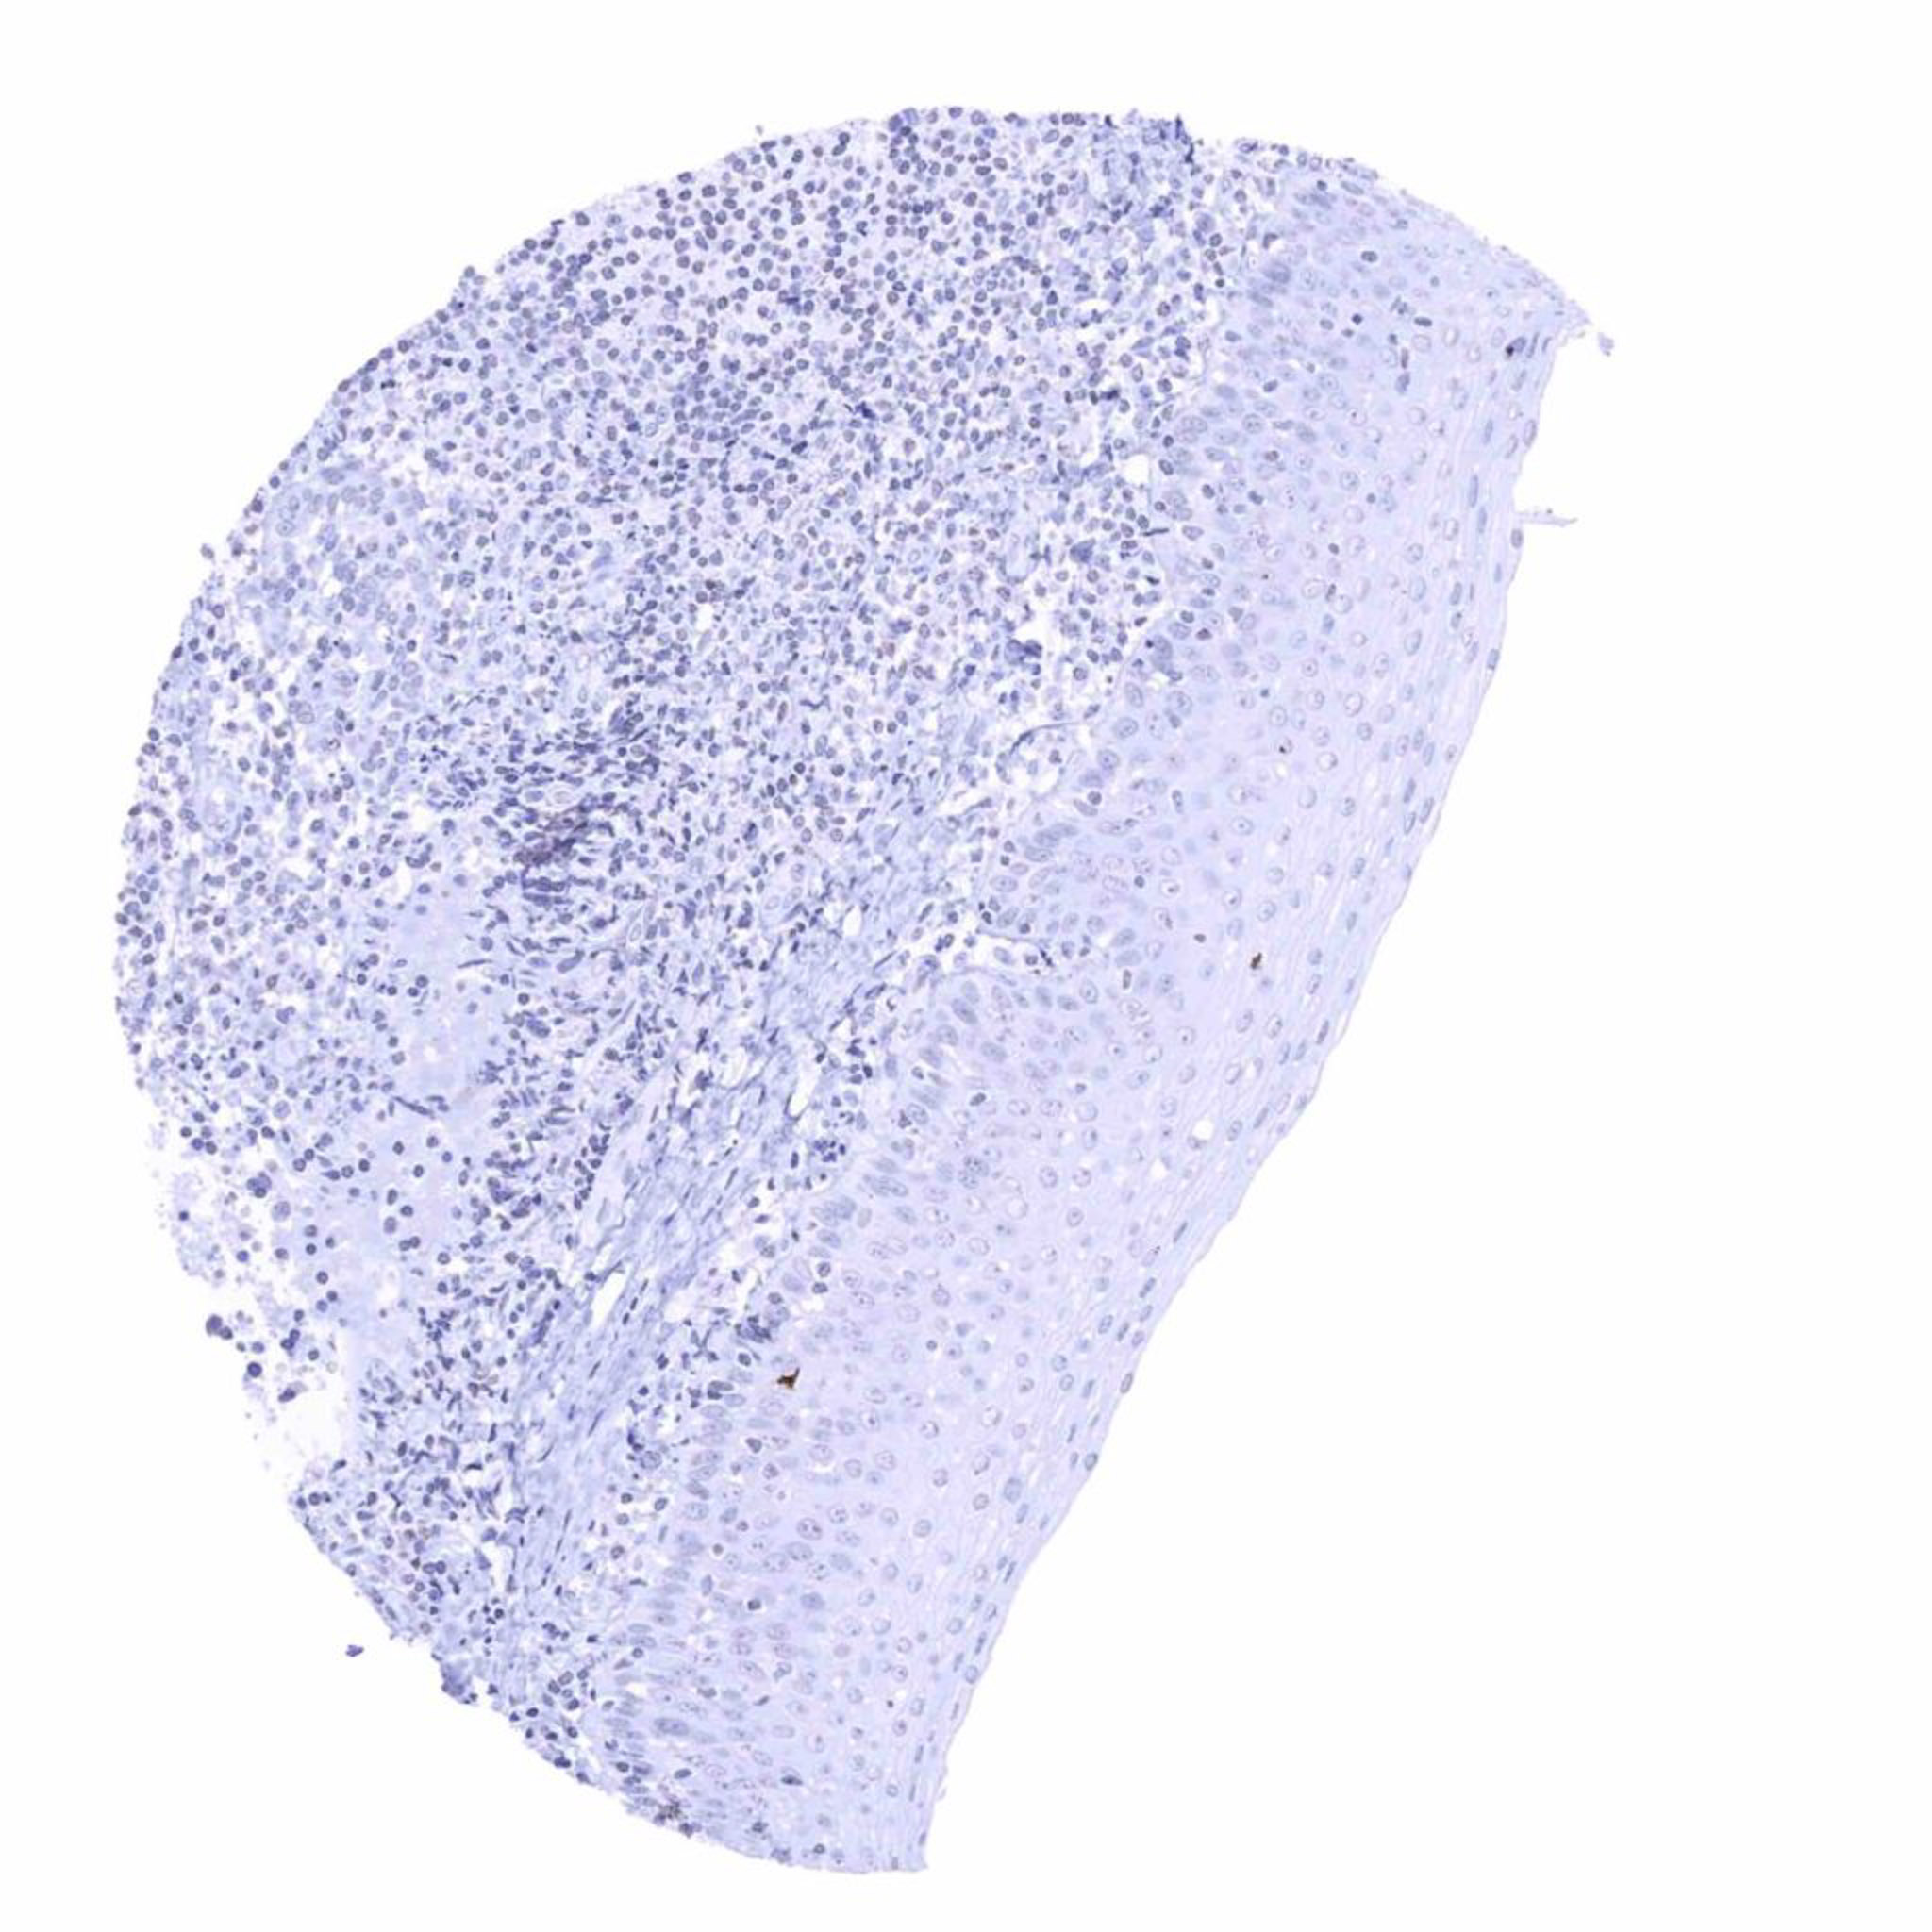

Lymph node

Tonsil